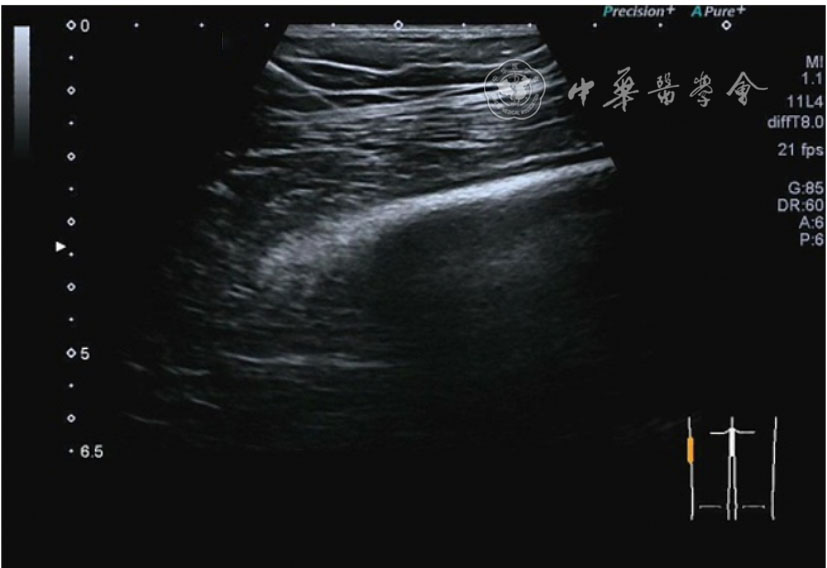

1.关节内表现。(1)骨改变。表现为骨末端或关节周缘出现的骨质局部突起改变,其后方伴或不伴有声影,多见于膝关节内侧缘和外侧缘(图1)。(2)软骨改变。股骨关节面改变可以在长轴及短轴切面显示,嘱患者屈曲膝关节,足平置于检查床,股骨滑车及股骨髁上半部分的关节面即可轻松显示。超声探查可见股骨负重面关节软骨发生不同程度的改变,轻者关节软骨浅侧边界模糊,重者可见关节软骨薄、缺失,软骨下骨缺损改变(图2)。(3)半月板外突。一般内侧半月板突出多见,外侧半月板突出比较少。半月板可见不同程度的外突,同时伴有膝内侧副韧带向外移位(图3)。半月板外周缘性滑脱是指半月板突出超出胫骨平台边缘的距离≥3 mm,其可引起一系列临床症状,早期诊断、早期治疗可以预防骨关节的进一步损伤。(4)交叉韧带损伤。可见前后交叉韧带增粗,回声减低(图4)。(5)髌上囊积液。膝关节是最容易发生积液的关节之一。患者仰卧位,关节积液最常见于膝关节上外侧,因为关节囊向髌股关节上外侧突出。髌上囊积液采用10~18 MHz的高频线阵探头于股四头肌腱纵断面及横断面扫查均可显示,探头频率取决于患者体型。超声可见低回声积液,慢性可伴有丛状滑膜增生(图5)。(6)脂肪垫水肿。脂肪垫在髌骨附着点处回声增强、增厚(图6)。

图1 关节间隙周边及关节骨赘形成超声图像

3.超声半定量评估。(1)骨赘超声半定量评估:患者仰卧位,膝关节伸直,探头纵切面置于膝关节内侧与外侧,自前向后移动探头以进行全面扫查。测量骨赘的厚度,并进行半定量分析。0级:无骨赘;1级:小骨赘,厚度<2 mm;2级:中等骨赘,厚度2.1~4.0 mm;3级:大骨赘,厚度>4.0 mm。(2)关节软骨超声半定量评估:患者仰卧位,膝关节完全屈曲。探头置于骨上方,检查股骨内侧髁、外侧髁和股骨滑车处关节软骨三个部位,分别进行横切面和纵切面检查,从近侧向远侧做全面扫查。检查时声束要垂直于股骨表面。关节软骨可按病变严重程度分为四级。0级:关节软骨呈均匀的无回声带,其浅侧和深侧边界清晰。1级:关节软骨浅侧边界不清和(或)内部回声增高。2级:①2A级,关节软骨局部变薄,缺损厚度<50%;②2B级,关节软骨局部变薄,缺损厚度>50%,但<100%。3级:关节软骨局部完全消失,伴或不伴有软骨下骨病变。(3)半月板突出分度:半月板外周缘与胫骨平台边缘之间的距离≥3 mm的突出视为病理变化,诊断为半月板周缘滑脱。按照突出程度分为三度:Ⅰ度,半月板外周缘与胫骨平台边缘之间的距离3~5 mm;Ⅱ度,半月板外周缘与胫骨平台边缘之间的距离>5~8 mm;Ⅲ度,半月板外周缘与胫骨平台边缘之间的距离8 mm以上。